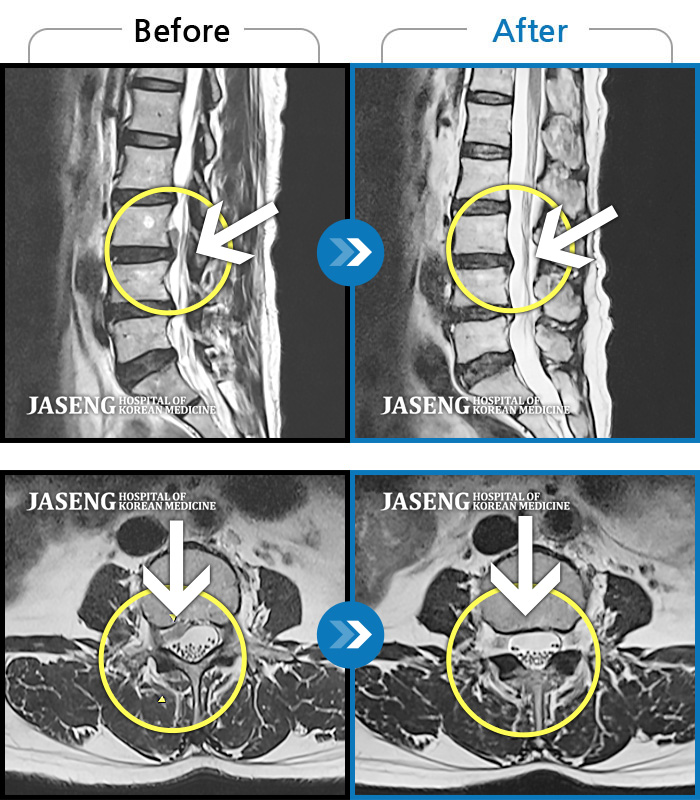

Before

After

환자에게 사전 동의를 받아 동일 조건에서 촬영되었습니다.

개인에 따라 치료 후 부작용이 발생할 수 있으니 의료진과 상담 후 치료를 진행하시기 바랍니다.

허리디스크로 인한 요통, 좌측 하지방사통

좌측 엉치에서 발까지 당기는 통증